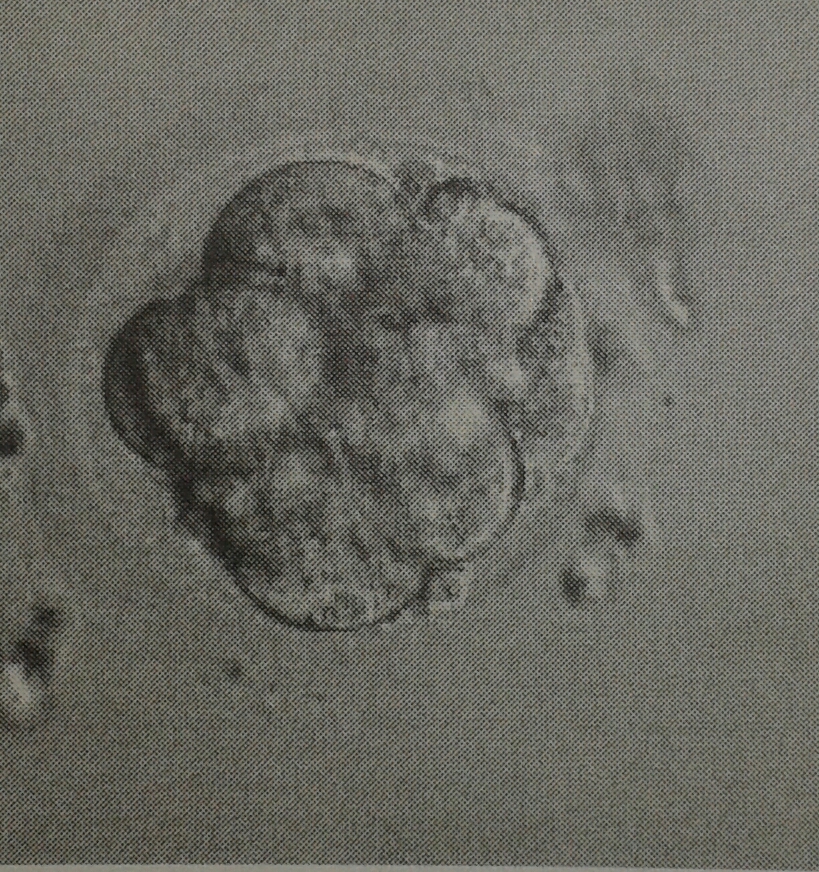

Anbei auch mal Bilder unserer Beiden .. ich hoffe so sehr sie sind noch bei mir *dd*

LG Manuela

Dateianhänge

20140620_175734-1-1.jpg

20140620_175728-1.jpg

05.05.14 PU 9 Eizellen, davon 8 reife EZ

06.05.14 8 EZ befruchtet ... 100% wow

09.05.14 ET von einem 8 Zeller und einem Morula ...

GMS 15, 5